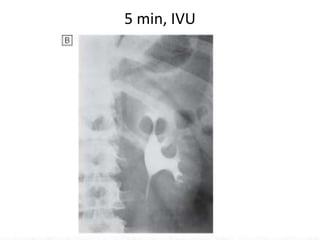

Intravenous urography (IVU)

• the technique provides excellent definition of the collecting

system and ureters, and remains superior to ultrasound for

examining renal papillae, stones and urothelial malignancy .

• X-rays are taken at intervals following administration of an

intravenous bolus of an iodine-containing compound that is

excreted by the kidney.

• The disadvantages of this technique are the need for an

injection, time requirement, dependence on adequate

renal function for good images, and risk of exposure to

contrast medium and irradiation.

5 min, IVU